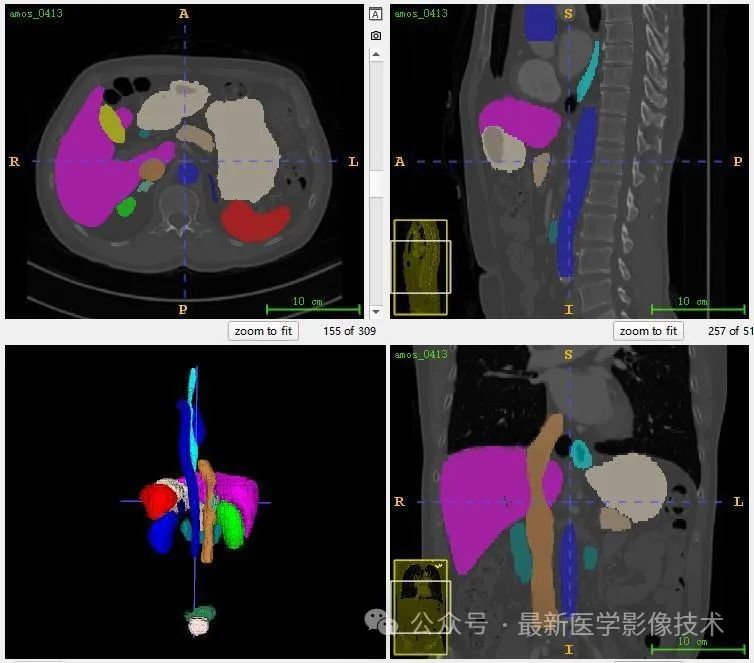

AMOS2022数据集示例说明,提供了 500 例 CT 和 100 例MRI 以及 15 个腹部器官的体素级别注释, 包括脾脏、右肾、左肾、胆囊、食道、肝脏、胃、主动脉、下腹部腔静脉、胰腺、右肾上腺、左肾上腺、十二指肠、膀胱、前列腺/子宫。请注意,某些数据点由于生理移除或由于未扫描身体部位而丢失了某些器官。

共500张CT和MRI,标注了15个器官(脾、右肾、左肾、胆囊、食道、肝、胃、主动脉、下腔静脉、胰腺、右肾上腺、左肾上腺、十二指肠、膀胱、前列腺) /子宫)呈现。请注意,某些数据点由于生理移除或由于未扫描身体部位而丢失了某些器官。

13、测试集分割结果